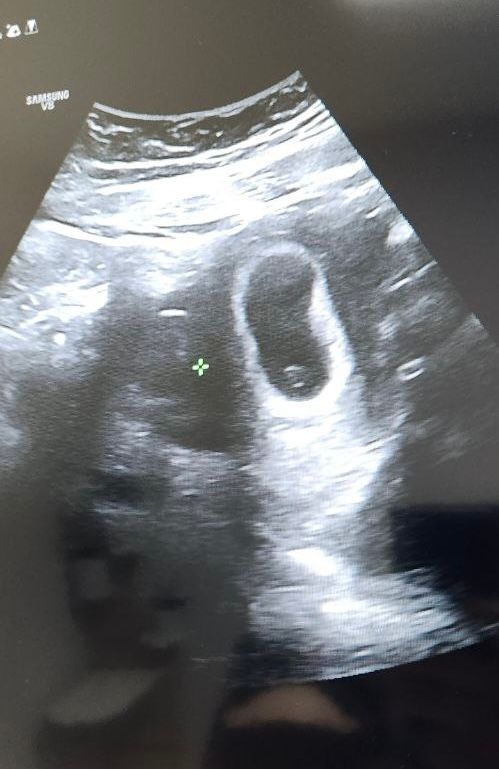

Елена

Здравствуйте, если ещё актуально, посмотрите пожалуйста нас❤️ я так понимаю, это скорее всего мальчик?)

09.12.2024